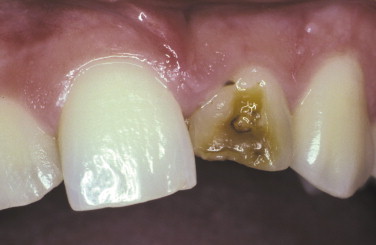

Diagnosis of this tooth?

Turner’s hypoplasia

What causes Turner’s hypoplasia?

A periapical inflammatory disease of the primary dentition causes hypoplasia of the underlying, developing deciduous tooth.